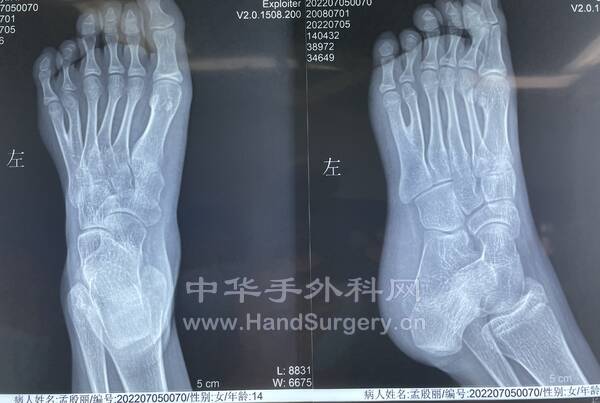

患者女性,14岁,先天双足多趾畸形。